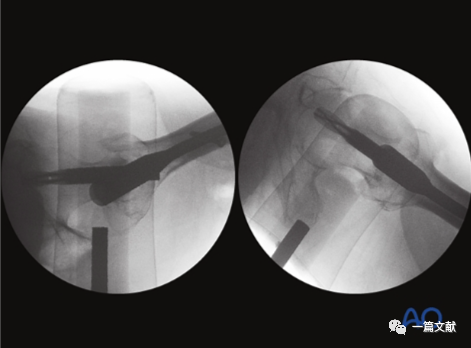

左侧正位片显示颈干角,右侧侧位片显示前倾角。

从侧位片基础上抬C臂机约15°即轴位片,如下:

下图左侧正位片与右侧的轴位片,显示了内固定的良好位置(位于头颈中心与髓腔中心)。需要注意的是这些标准的术中透视图像,只有在良好骨折复位的基础上才能获得。

只有如下图右侧的轴位片图像才能判断内固定在头颈骨块中的位置(左侧为侧位片)

同一患者的侧位像与轴位像的内固定透视图像如下图: